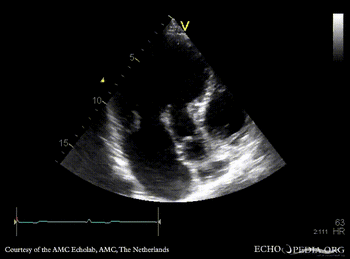

| Marfan Syndrome

| Courtesy of: AMC Echolab, AMC, The Netherlands

| PLAX: dilated aortic root, redundant mitral valve leaflets

PLAX: dilated aortic root